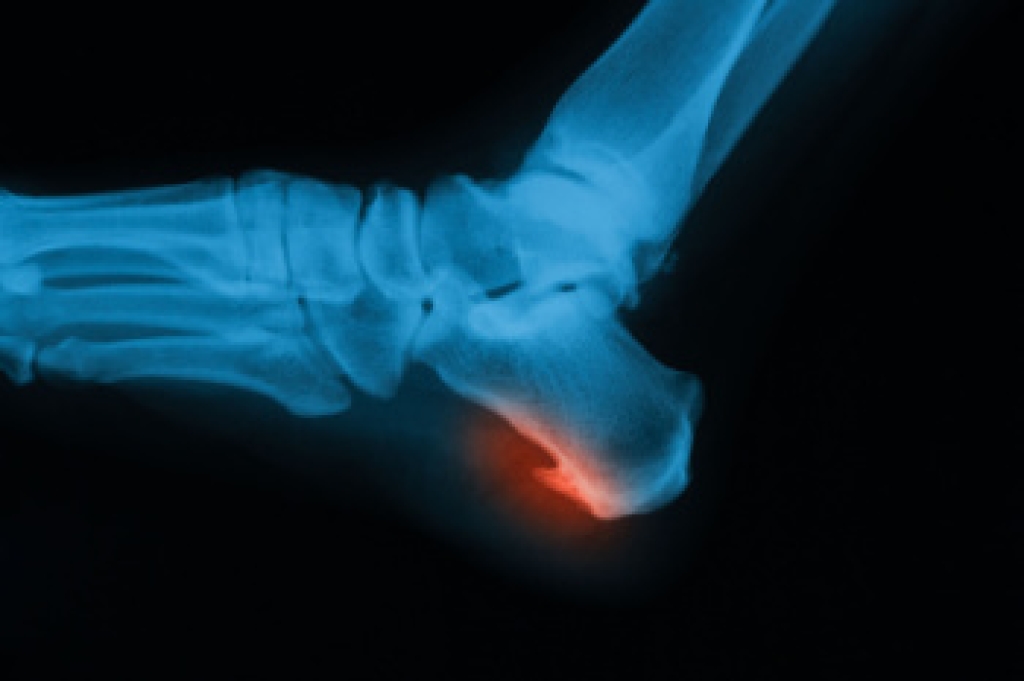

- Vertical talus, where the talus bone forms in the wrong position causing other bones in the foot to line up improperly, the front of the foot to point up, and the bottom of the foot to stiffen, with no arch, and to curve out.